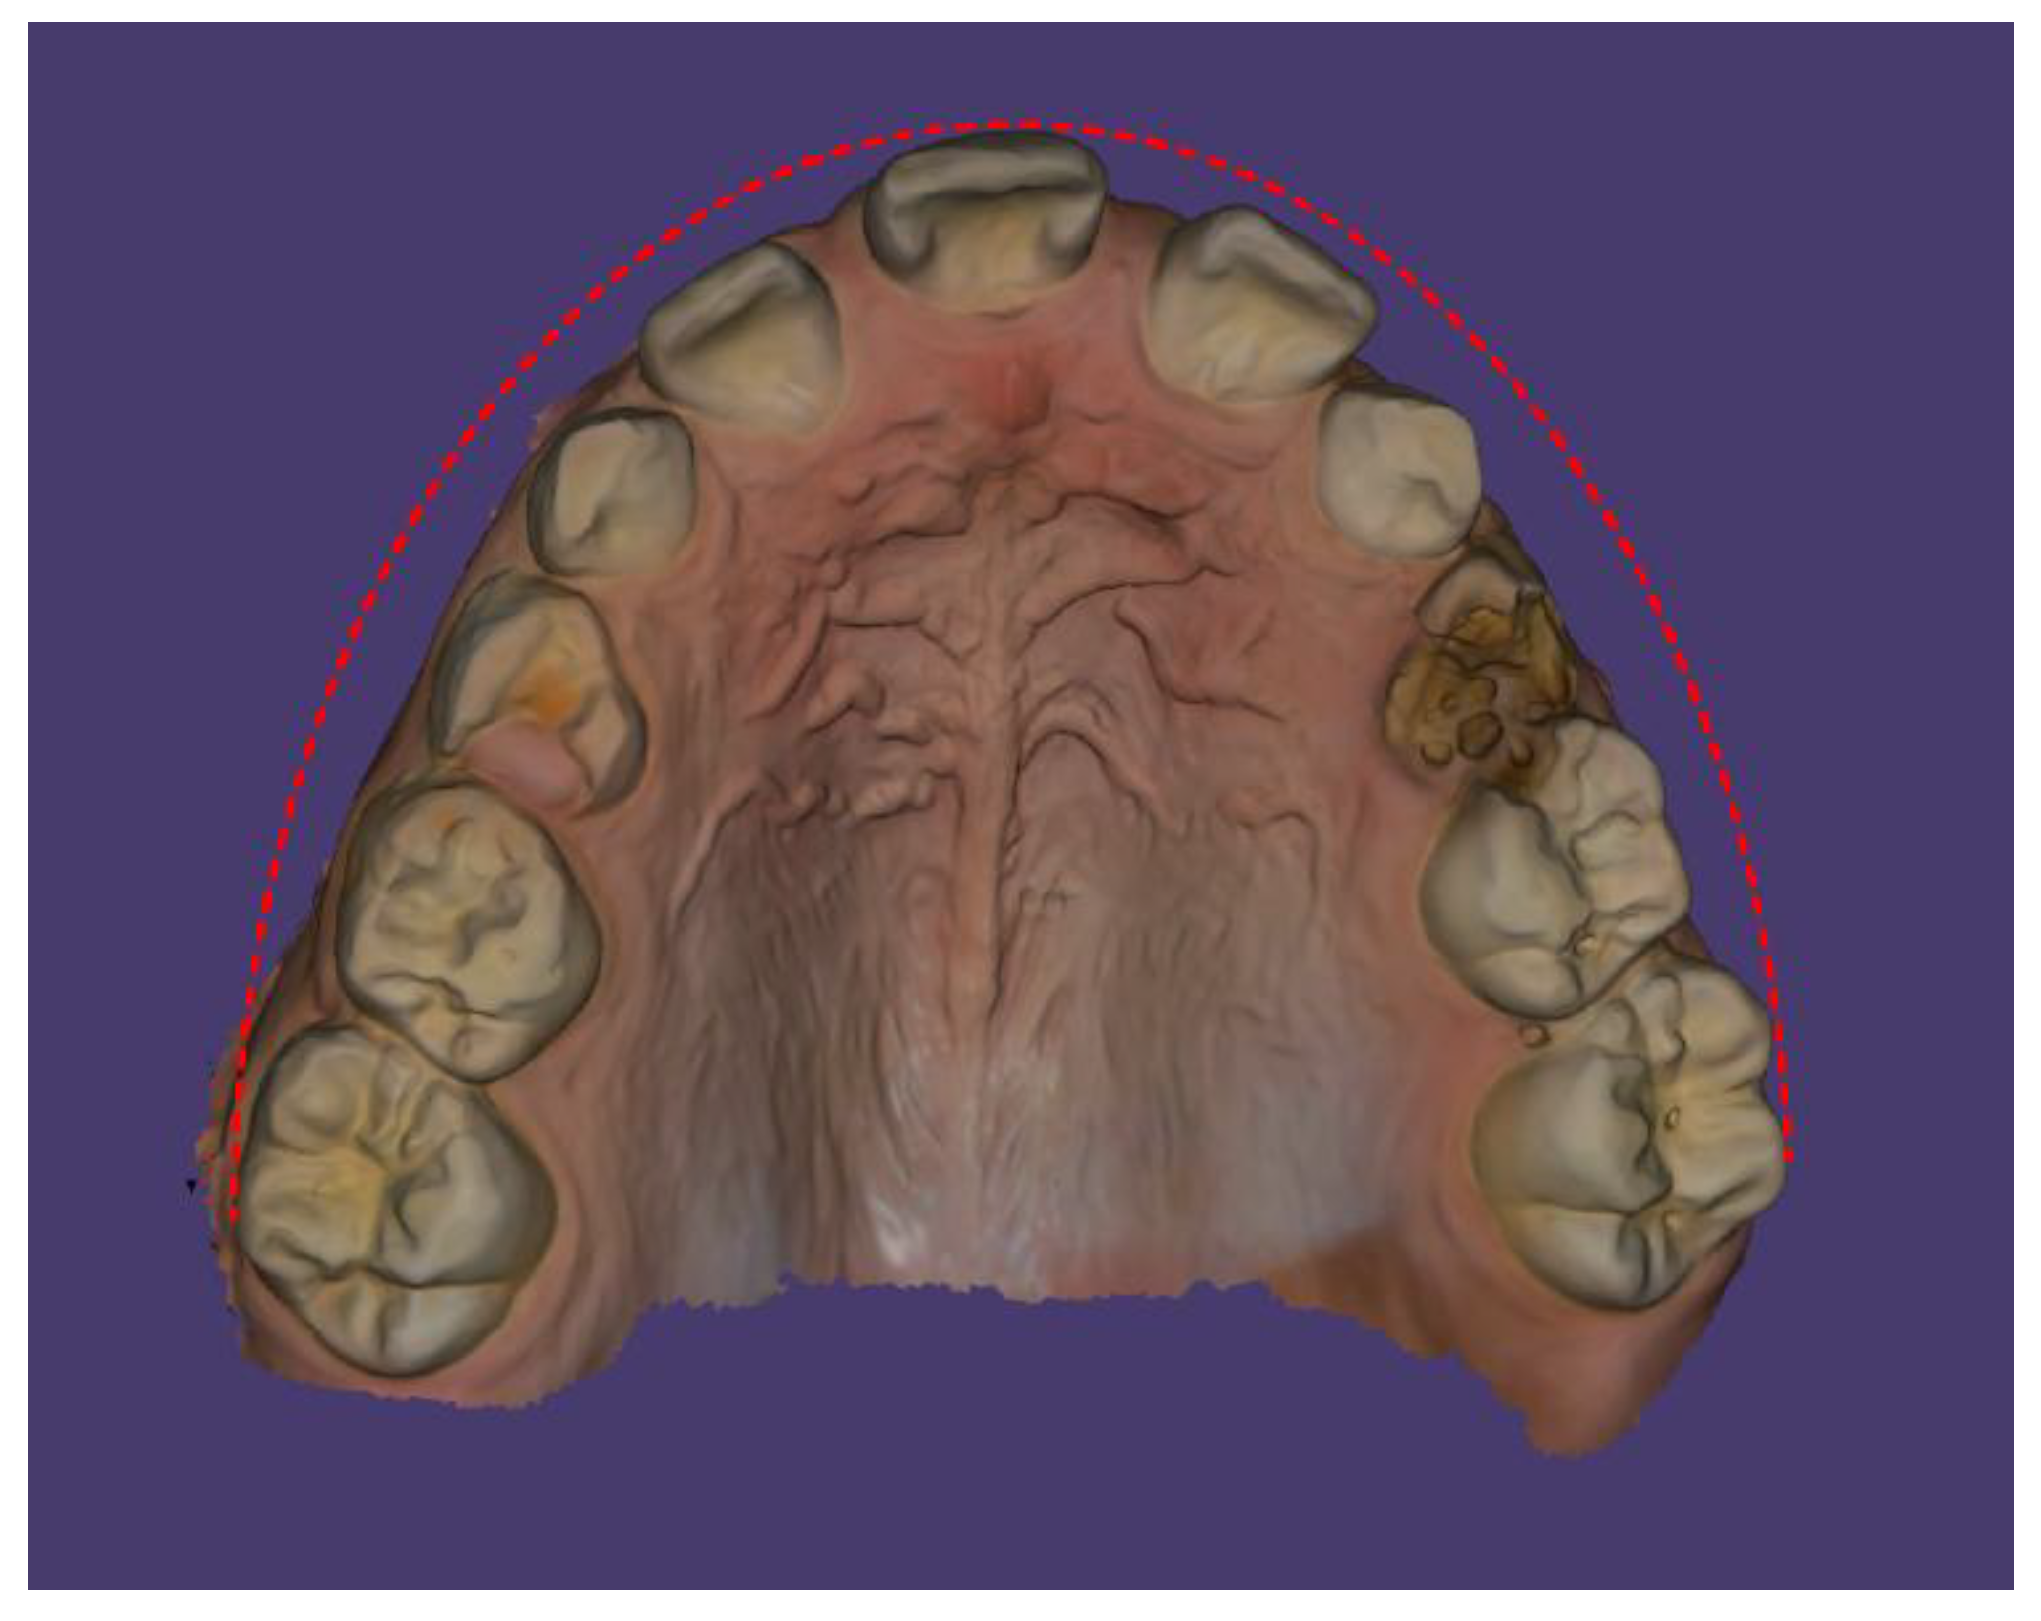

Case Description